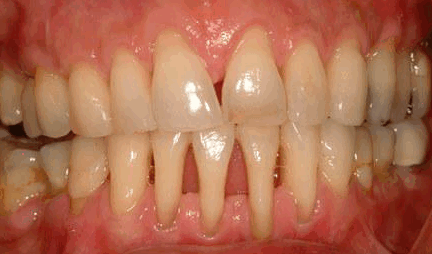

Хронический пародонтит

Такая форма заболевания является самой тяжелой и характеризуется фактической утратой кости и мягких тканей пародонта, поддерживающих зубы. Результатом становится смещение и сильная подвижность зубов. Для предотвращения дальнейшего распространения инфекции может потребоваться даже их удаление. Симптомы хронического пародонтита включают:

- сильную рецессию десны

- глубокие пародонтальные карманы

- подвижность зубов

- нарушение окклюзии